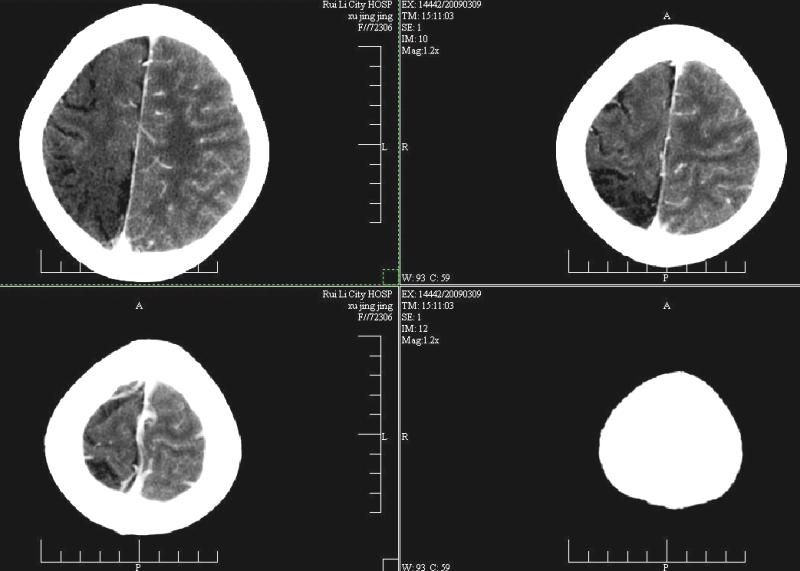

支持楼主!右侧强化明显较左侧低.可能血管引起的吧.

支持楼主!右侧强化明显较左侧低.可能由血管发育不良引起的吧.

支持大脑发育不全----右侧大脑中动脉较对侧细小。建议cta 或mra 检查